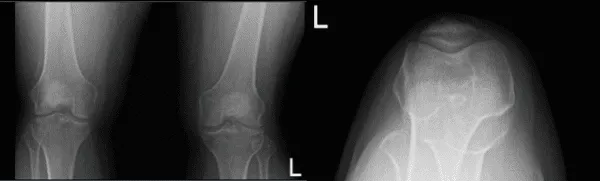

Se realizó una resonancia magnética y una radiografía, que muestran una rotura del menisco lateral. Hablamos sobre las opciones de tratamiento y el paciente optó por el manejo quirúrgico. Hablamos sobre los riesgos, beneficios y complicaciones de la cirugía. Hablamos sobre la posible reparación meniscal frente a la meniscectomía. El paciente lo entendió y firmó un consentimiento informado.